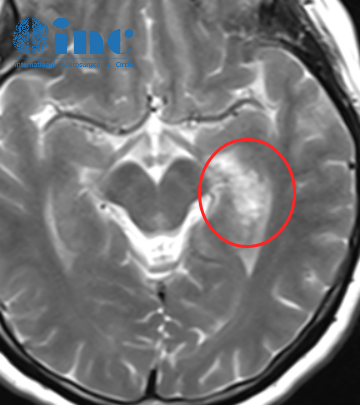

48岁男性--左侧额顶颞岛叶胶质瘤

48岁的马先生一年前偶然查出左侧额顶颞岛叶较大占位-低级别胶质瘤,无任何症状,但病变大小已经达到了86×64*41mm。长在功能区,术后可能影响肢体、语言、意识等,所以不敢贸然做手术,一直吃中药治疗。然而当再次复查时,病变体积已经增大到90mm多,达到一个橙子体积小大。眼看着症状日益明显,马先生决定继续求医,希望能尽快手术。当通过INC国际神经外科医生集团找到巴教授时,又会得到怎样的回复?

巴教授评估回复

具体原因是因为我不想在神经方面使患者的情况变得更糟糕,而且正如我所说的,(如果进行手术)言语和运动方面功能障碍存在更高的风险。我现在看到他状态也很好,这就是(我不建议手术的)原因。我认为我们可以在患者接受肿瘤治疗后,明年再讨论手术的必要性。